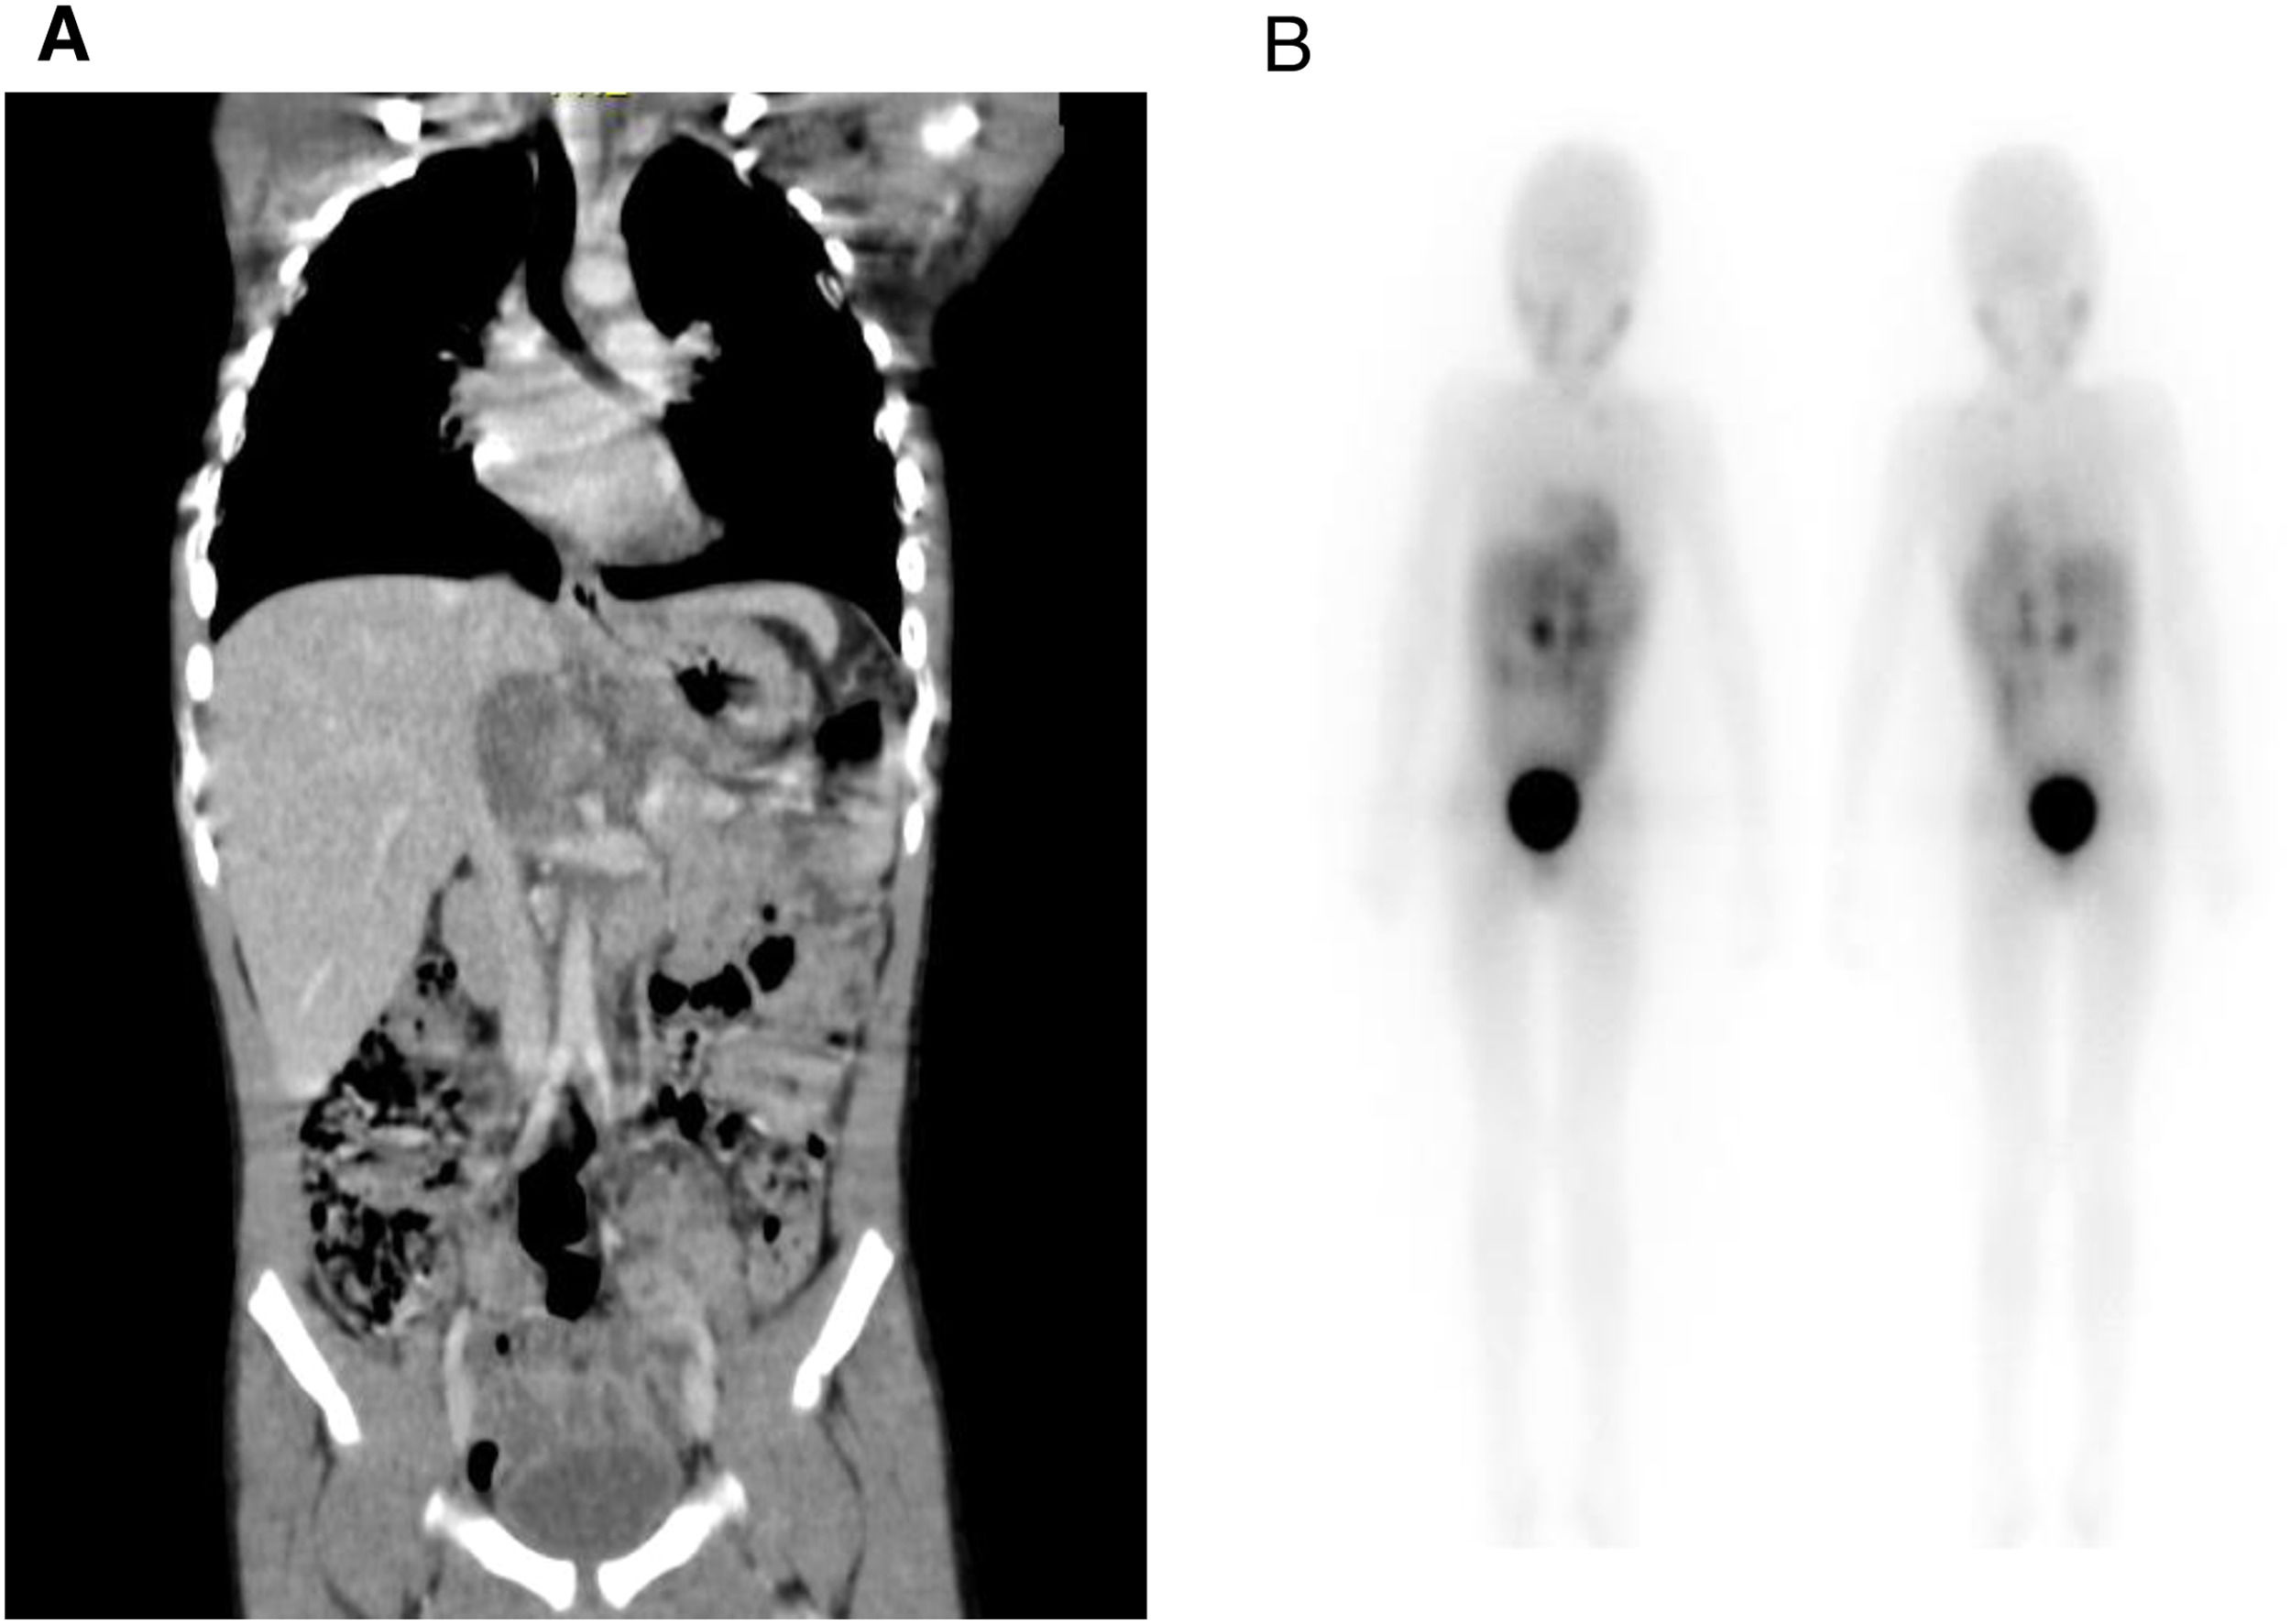

After 4 months of radiotherapy, the patient developed a new brain lesion. A palliative treatment was initiated. The patient died after four years of diagnosis (Fig. 2).

(A) Scintigraphy using MIBG¹³¹ shows accumulation of radiopharmaceutical built-up in various areas: near the frontal bone, affecting the right renal vessels, celiac trunk, and superior mesenteric artery, extending caudally in the retroperitoneum. Nodules are present behind the cecum, alongside the psoas major and right iliacus muscles, as well as in the metaphyseal areas of the left humerus and tibia. Additionally, nodules are observed in the proximal metadiaphyseal areas of the femurs and left ischium. The images on the left depict the anterior and posterior MIBG-131 pre-infusion scans, while those on the right show the same angles 48 h after drug infusion.